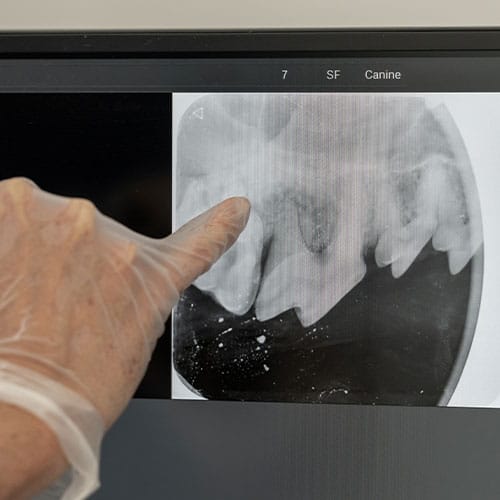

Dental Radiographs (X-rays):

- X-rays are crucial for diagnosing issues not visible to the naked eye, such as tooth root abscesses, bone loss, or retained roots. They guide our treatment plan for optimal outcomes.